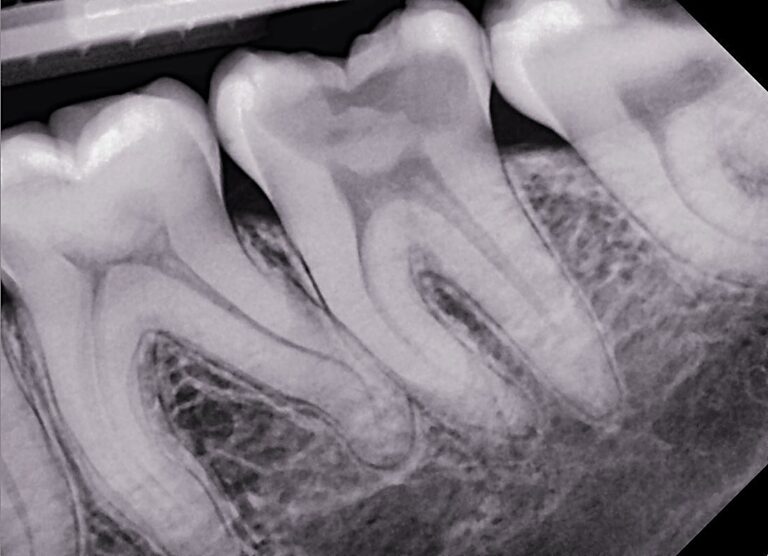

Cyfrowe zdjęcia punktowe zębów